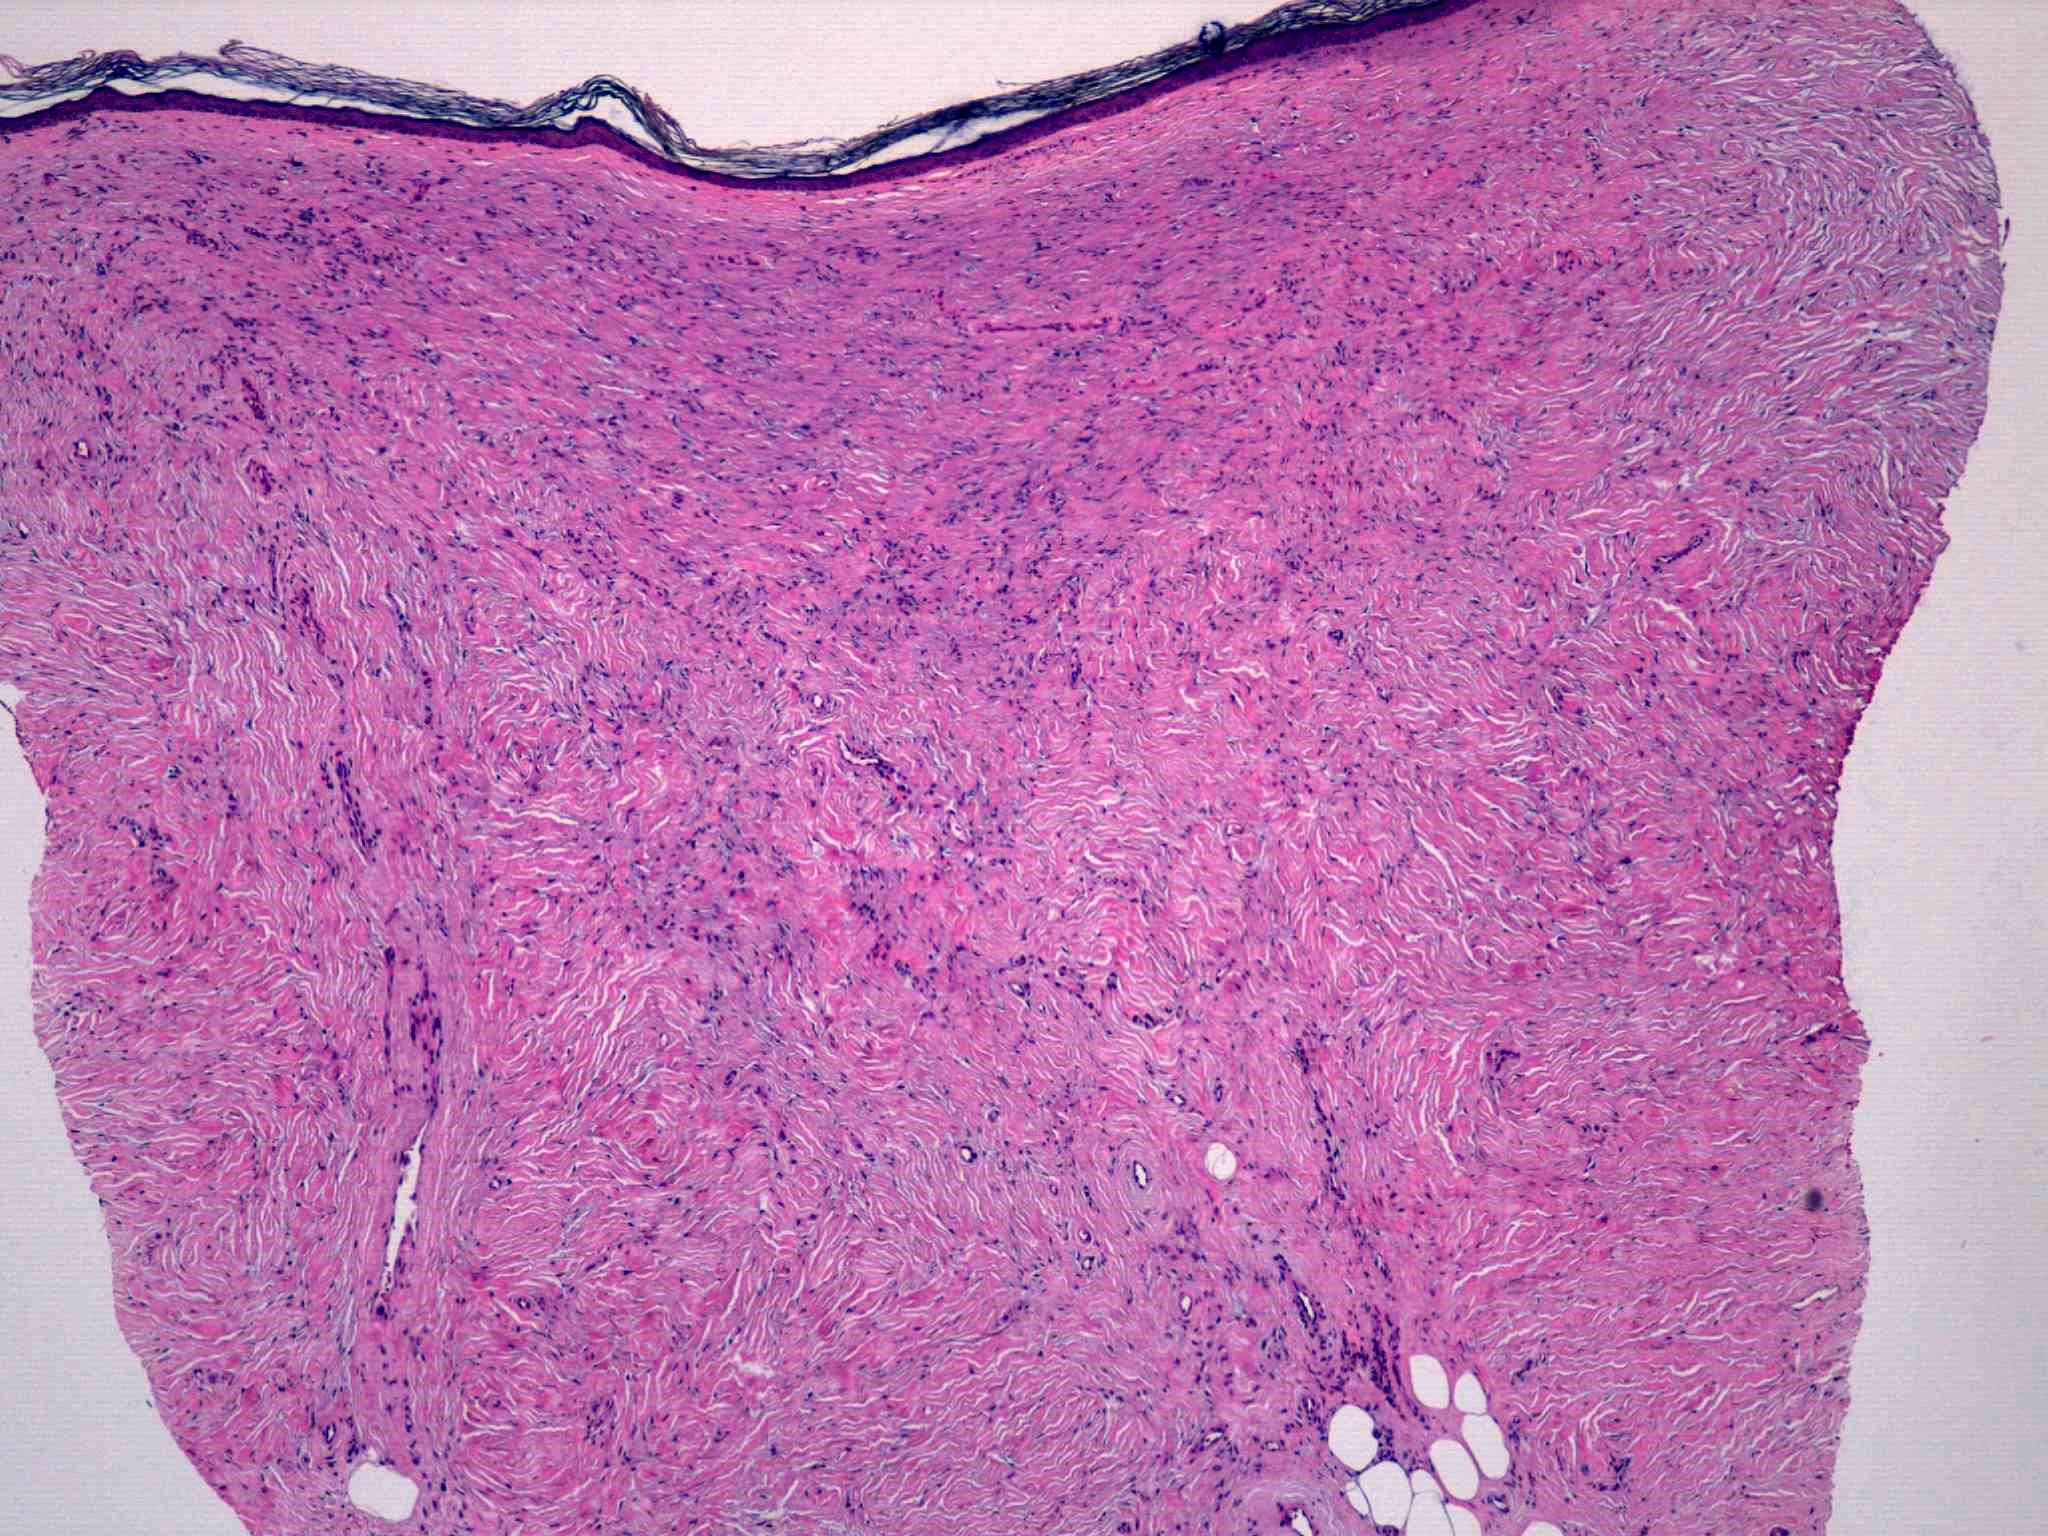

27 -- image_2011y10m04d_15h23m36s.jpg